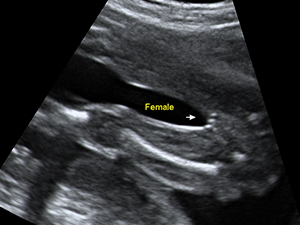

女性

懷孕20週的女性胎兒性器官(箭咀)